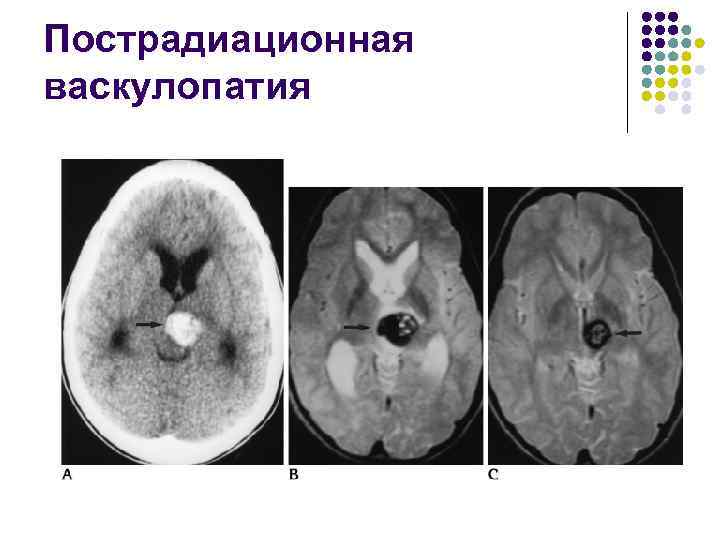

Пострадиационная васкулопатия l l Является следствием лучевой терапии опухолей мозга Радиация оказывает прямое повреждающее действие на сосуды

Пострадиационная васкулопатия